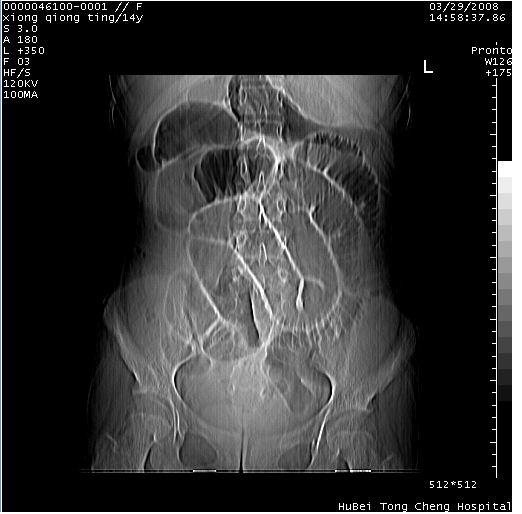

中下腹及盆腔ct轴位平扫+增强扫描(层厚10mm,螺距1.0,重建间隔10mm),图像如下:

(注:患儿检查当日上午9时口服胃肠道对比剂,下午3时许行ct扫描检查,未行对比剂直肠保留灌肠,检查当日患儿腹泻)

中下腹及盆腔ct轴位扫描(ps+ce)提示:腹部肠管明显充气扩张,并见数个不同宽度之气液平面;疑不全性肠梗阻或肠郁张。临床会诊考虑为患儿腹泻,肠郁张所致;后来未经特殊处理,患儿大便恢复正常,亦无腹胀。